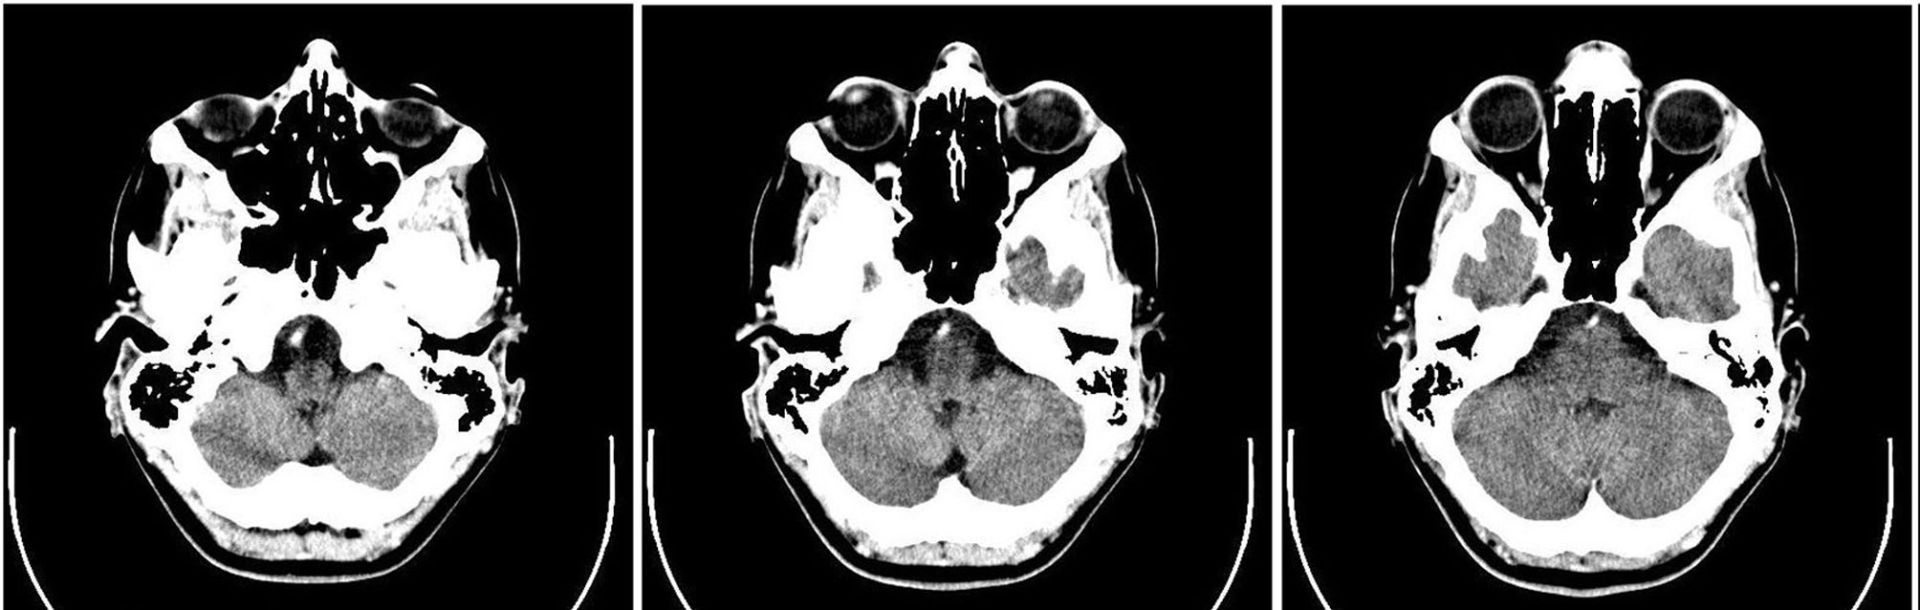

Within the brain there is a permeable membrane known as the blood brain barrier, which drugs must cross to be able to reach the areas needed to have an effect.

Our research has enabled the construction of an in vitro model of the blood brain barrier, and a method of use of the in vitro blood brain barrier in order to test whether drug candidates can cross through the barrier and so be able to have a therapeutic effect on a patient.

The barrier of the present invention has improved physiological relevance, and therefore is more useful for research into the permeability of the barrier to various molecules, specifically applications in assessing permeability of the barrier to candidate drugs.

The Blood brain barrier model produced as part of this research provides an improved simulation of the effect of the blood brain barrier in the brain and so can provide an improved indicator of the potential effectiveness of drugs that are required to reach the brain to have therapeutic effect.